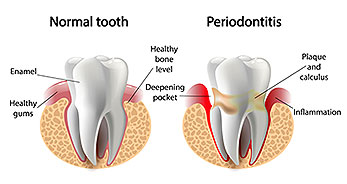

Periodontal disease—commonly known as gum disease—is very common and affects many adults. It can range from mild gum inflammation to more advanced conditions that damage the gums and bone supporting the teeth. In severe cases, tooth loss may occur.

Gum disease is caused by bacteria that naturally live in the mouth. These bacteria form a sticky film called plaque on the teeth.

If plaque is not removed through brushing and flossing, it hardens into tartar, which can only be removed by a dental professional.

Over time, plaque and tartar lead to gum inflammation, infection, and bone loss.